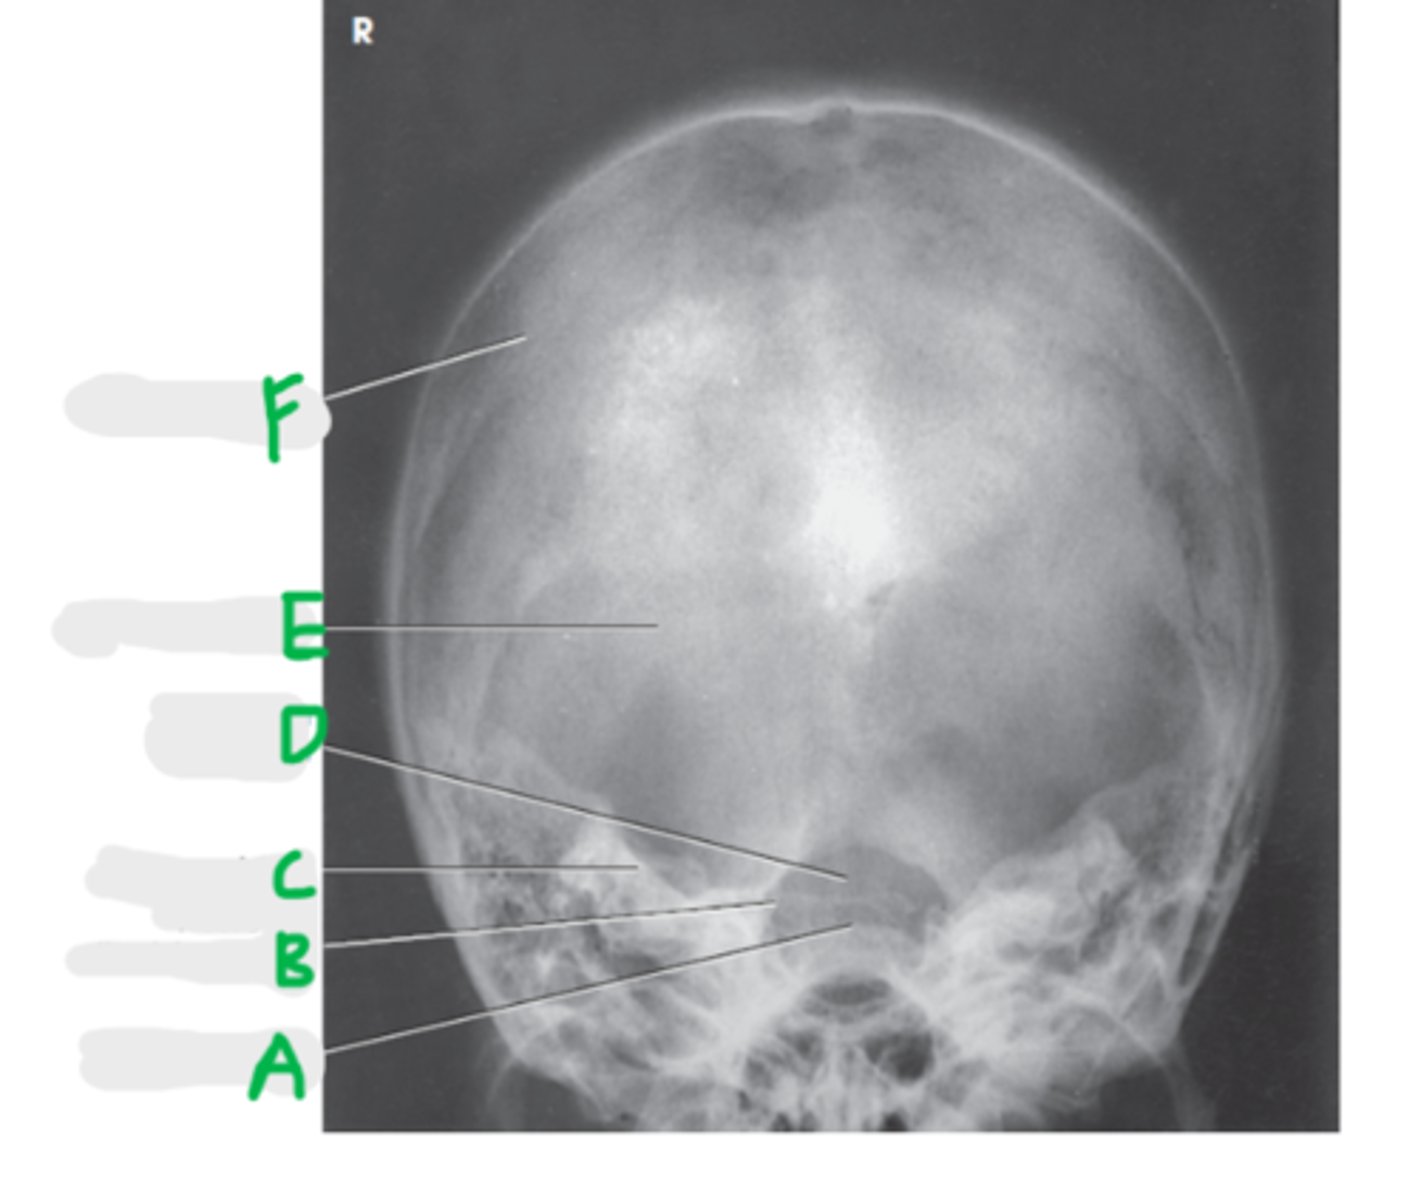

Dorsum sellae

A

Posterior clinoid process

B

Petrous ridge

C

Foramen magnum

D

Occipital bone

E

Parietal bone

F

AP axial (Townes Method)

What projection is this?